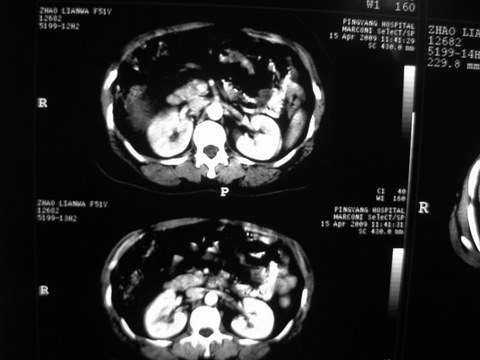

患者 女 51岁 两天前感觉上腹疼,无明显诱因,b超示肝右叶囊实性占位,边缘清楚,其内回声不均匀,ct增强如图,大家看看是什么 ,病人一年前及两月前b超检查只是提示胆囊炎

外院术后,证实肝癌合并出血

特点:1,病灶发展迅速,(2月前正常)[br] 2,囊实性,且并边界清晰光滑,呈右后叶赘生性。囊性区无强化,实性部分较多轻度强化,边界欠清。考虑囊腺癌或囊腺瘤。

出病理 中分化肝细胞癌合并出血